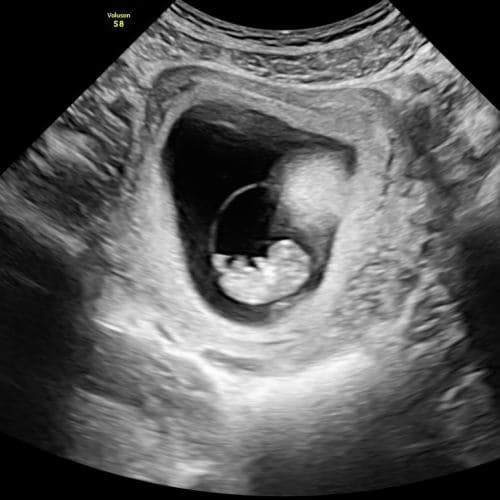

Við bjóðum uppá sónarskoðanir á meðgöngu, snemmsónar, tvívíddar- og þrívíddarsónar og stuttan 15 mínútna sónar.